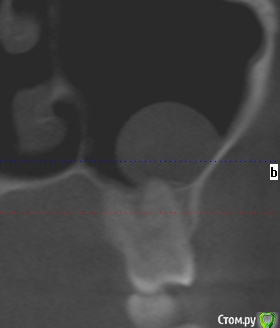

Добрый день коллеги,плановое удаление 8 зубов ,верхние в гайморовой ,что за образование в левой жалоб нет никаких.Что вы делаете при вскрытии пазухи?